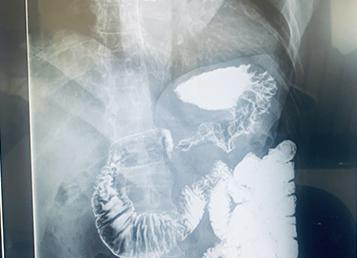

Рентген с барием тонкого кишечника

Пассаж бария идет сверху вниз

Пассаж сульфата бария по кишечнику происходит следующим образом. Через час контраст достигает тонкого кишечника. Через три часа он находится в переходе между тонким и толстым кишечником. За шесть часов барий попадает в восходящий отдел ободочной кишки. Через двенадцать часов – добирается до сигмовидной кишки, а через 24 часа – до прямой.

Таким образом, в норме время пассажа составляет приблизительно сутки.